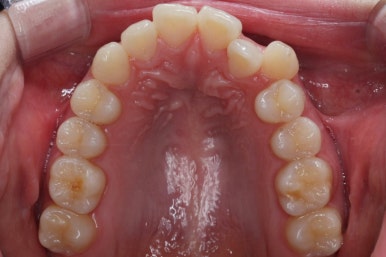

부산부정교합 키다리아저씨치과에 처음 내원하셨을 때의 입안 모습입니다.

위아래 앞니가 삐뚤고 특히 왼쪽 위 송곳니는 밖으로 두드러져 덧니 양상입니다. 윗니는 덧니쪽으로 쏠려 있어서 치열의 중앙이 맞지 않습니다.

윗니들만 보면 이런 모습으로 변해가고 있습니다.